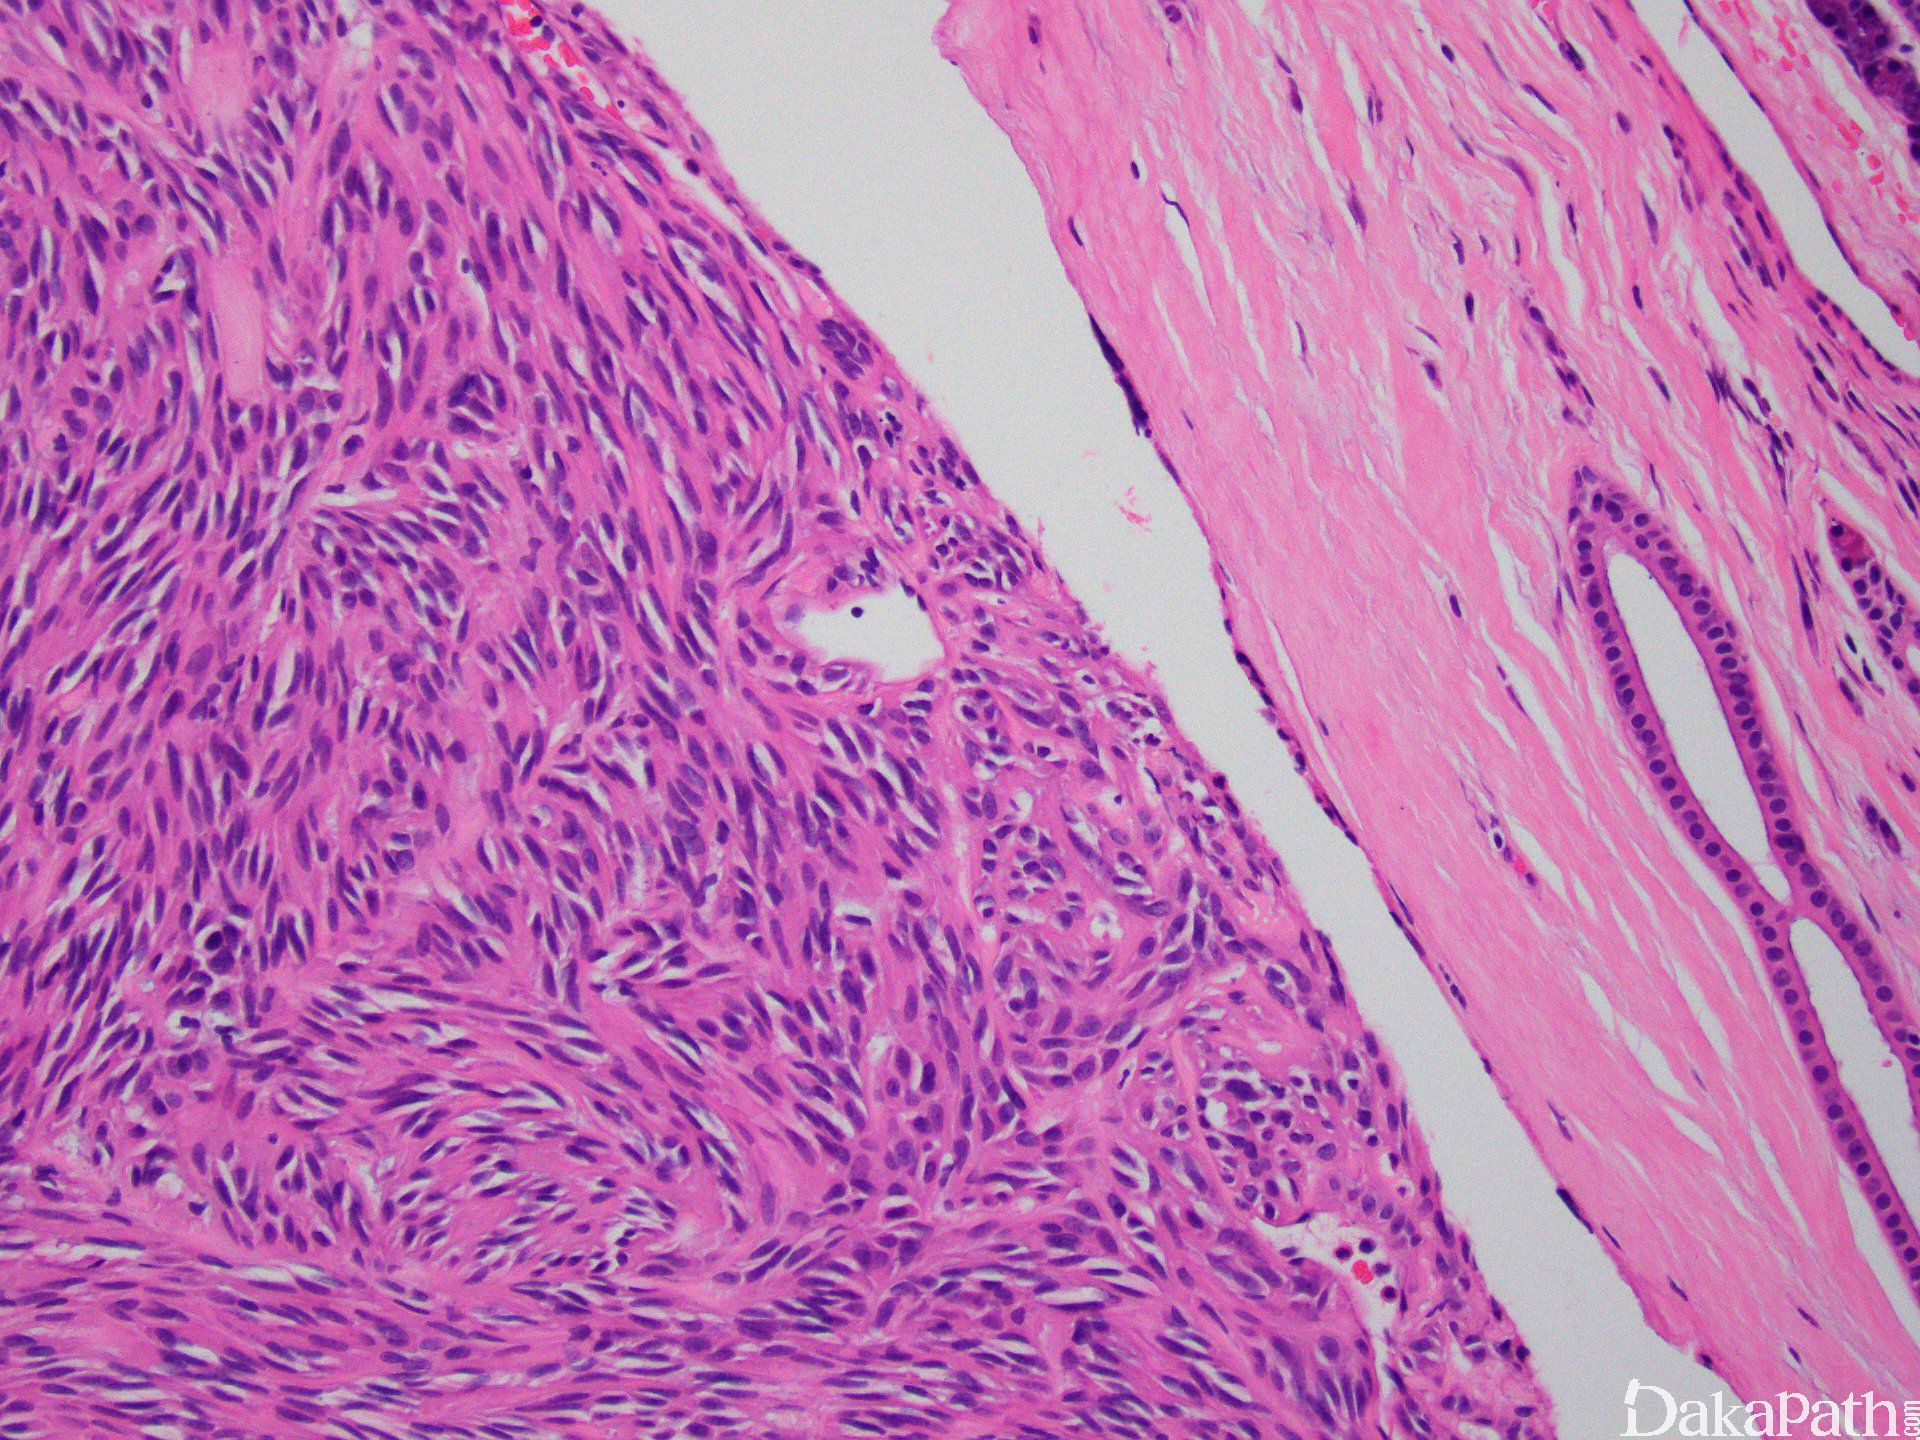

- 罕见的病变,可发生于任何年龄的任何部位,常表现为单个真皮或皮下小结节,很少位于皮下组织,界限清楚;

- 肌上皮细胞形态多样,可为短梭形,可呈上皮样,胞质从嗜酸性到苍白,也可透亮;

- 间质可伴纤维化、透明样变或黏液变性。